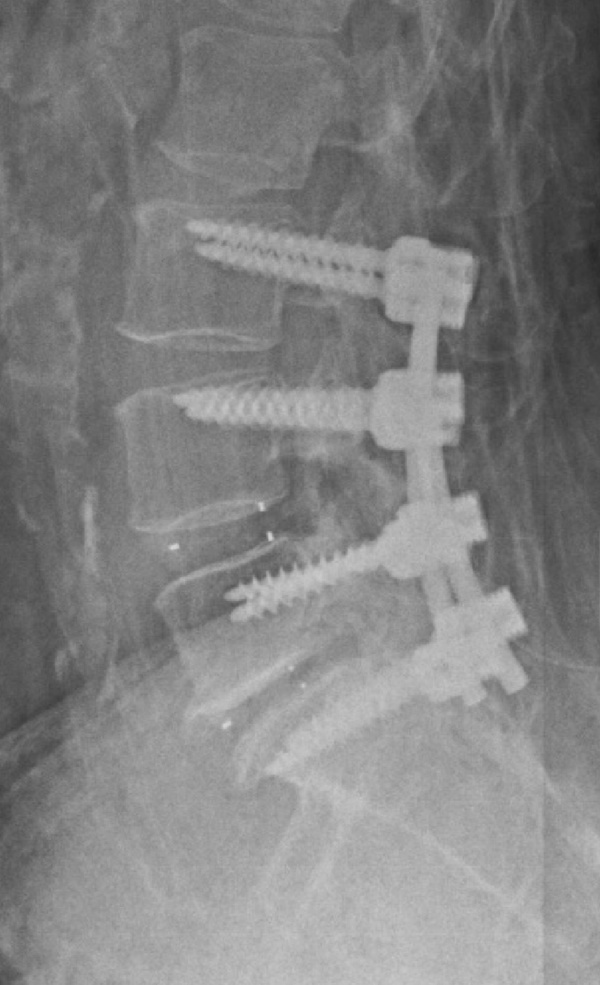

ESTENOSIS DE CANAL LUMBAR: para la resolución de este importante problema debemos liberar el canal lumbar, que se encuentra estrechado con compresión de las raíces nerviosas o la médula y en función del caso, realizar una ARTRODESIS VERTEBRAL (fijación de las vértebras para que no recidive la lesión). Este tipo de cirugía precisa ingreso de 4-5 días y la recuperación va desde 6 semanas a 3-4 meses por lo general.

Artrodesis lumbar